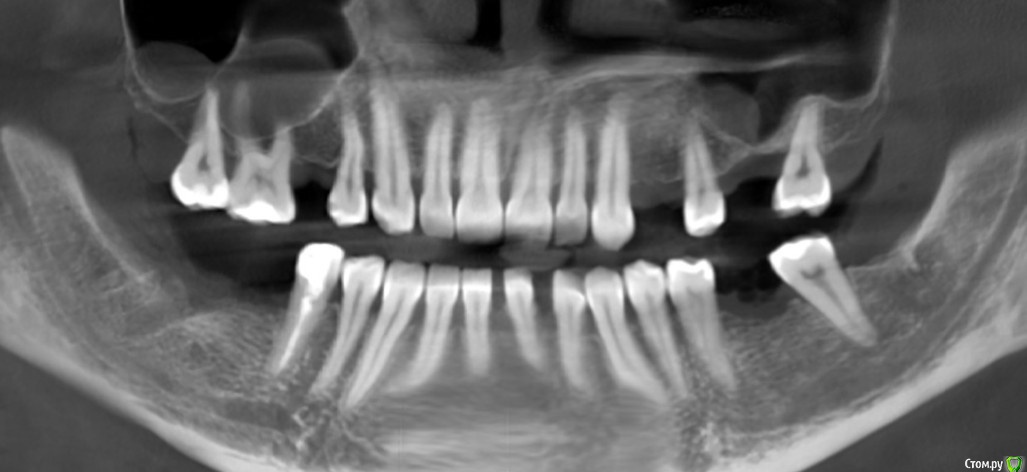

Irina_S Опубликовано 1 мая, 2017 Поделиться Опубликовано 1 мая, 2017 Уважаемые специалисты по жизненному циклу зубов и знатоки особенностей их поведения! Формулирую обращение именно так, потому что не знаю точно, какая именно стоматологическая специализация предполагает максимальную информированность по интересующему вопросу.Если ошиблась с выбором ветки форума, огромная просьба к модераторам перенести в нужное место! Моя история.В августе прошлого года был удалён нижний правый 7-й зуб. Была боль и опухание вокруг. Врач сказал, что ткани вокруг размягчены, оставлять нет смысла, будет плохо держаться. Зуб удалили, поставили дренаж. Десна затянулась за пару недель.В сентябре заболел верхний левый 6-й зуб. Была неудачная попытка лечения с диагнозом обострения периодонтита. При вскрытии каналов зуб был перфорирован и восстановлению по мнению всех врачей, у кого консультировалась, не подлежал. Удалили его в ноябре.Параллельно уже стала интересоваться имплантацией. Врач, удалявший зуб, сказал, что на это место раньше 4-х месяцев ставить ничего нельзя. Всё должно зарасти и уплотниться. Тем более, что десна там затягивалась гораздо хуже.В итоге из-за всех проводившихся манипуляций я с сентября почти всю пищу ем в измельчённом на блендере состоянии. Через блендер не проходят только те продукты, которые изначально не твёрдые и однородные. С левой стороны имеются соприкасающиеся 7-е зубы, но жевание ими больше дискомфортно, чем функционально. В остальных зубах, которые и до ухудшения жевательной способности не слишком сильно участвовали в пережёвывании, периодически появляются ощущения, которые сложно описать. Это не боль, а скорее больше похоже на что-то вроде онемения. Особенно чётко это ощущается по утрам после сна.Тем не менее, ситуация с моим питанием исключительно измельчённой едой, видимо, никаким образом не воспринимается серьёзно различными врачами, с которыми за это время общалась. Одни запросто предлагают перед имплантацией пройти курс ортодонтического лечения сроком не менее года. Другие говорят, что есть места, в которые нужно подсыпать костную ткань, и имплантацию там можно будет делать только через полгода, а это значит., что ещё плюс 3-4 месяца будет приживаться имплантат,, и только после этого появится хотя бы временная коронка.А ещё по мнению большинства ортопедов все коронки на имплантаты нужно ставить одновременно. То есть даже если где-то и можно установить имплантат раньше, то жевательная способность у восстанавливаемого зуба появится всё равно одновременно с остальными. В связи с этим у меня вопрос: как долго могут находиться зубы без жевательной нагрузки? Прикрепляю две панорамы из КТ с разницей в два месяца. Возможно, это поможет оценить какую-то динамику.Благодарю за терпение при прочтении и буду ещё больше благодарна за ответы! Ссылка на комментарий

колесников Опубликовано 1 мая, 2017 Поделиться Опубликовано 1 мая, 2017 Чем дольше будете ждать,тем меньше костной ткани будет в в областях предполагаемой имплантации,16,17 выдвинуться ещё больше,проблемы с внчс примут функциональные изменения. Необходимо имплантироваться как можно скорее ,если хотите несъёмные конструкции,либо съёмный протез на нч. Зубы 17,16 сильно выдвинулись,необходим очный осмотр. Самый сложный участок в плане имплантации ,область 26. Все решаемо. Ссылка на комментарий